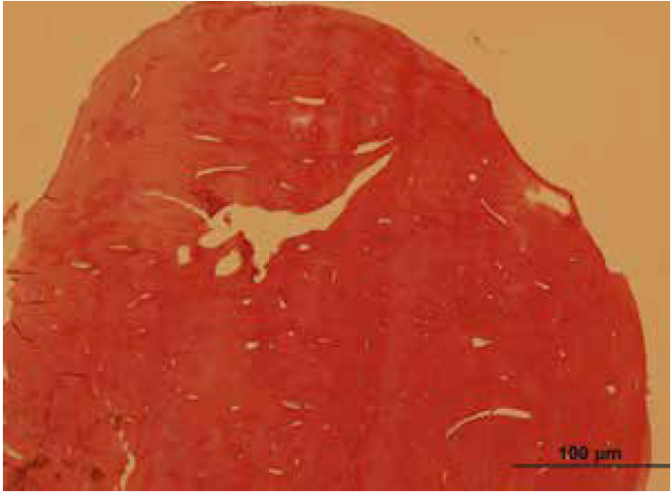

An 8-years-old boy reported to the Department of Oral and Maxillofacial Surgery, Ondokuz Mayis University with a chief complaint of hard swelling in the left posterior region of the mandible. The patient was physically healthy and any systemic condition was not detected during anamnesis. The swelling was not associated with any pain, discharge, fever, paresthesia, or difficulty in mastication. The patient did not recall or confirm any history of trauma or infection in that region. On clinical examination, a solitary, non-pulsatile and approximately 1.5 cm in diameter, bony mass was palpated at the left angle region of the mandible. The tumor found fixed to the underlying bone and the skin overlying the tumor was in a healthy appearance. The panoramic radiography and cone beam computed tomography (CBCT) scan showed a well circumscribed, radiopaque mushroom like image located on the left angle of the mandible (Figure 1, Figure 2). The 3D reconstruction of the computed tomography image revealed a pedunculated homogeneous bony mass attached to the left angle of the mandible (Figure 3). The lesion was completely excised using an extra oral approach under general anesthesia (Figure 4). The surgical specimen was submitted for histopathological examination. Histopathological examination revealed a sclerotic lamellar bone nodule with almost no intertrabecular space (Figure 5). These features confirmed the final histopathologic diagnosis to be peripheral osteoma. The post-operative course was uneventful with a satisfactory healing (Figure 6) . The patient is still under follow-up.